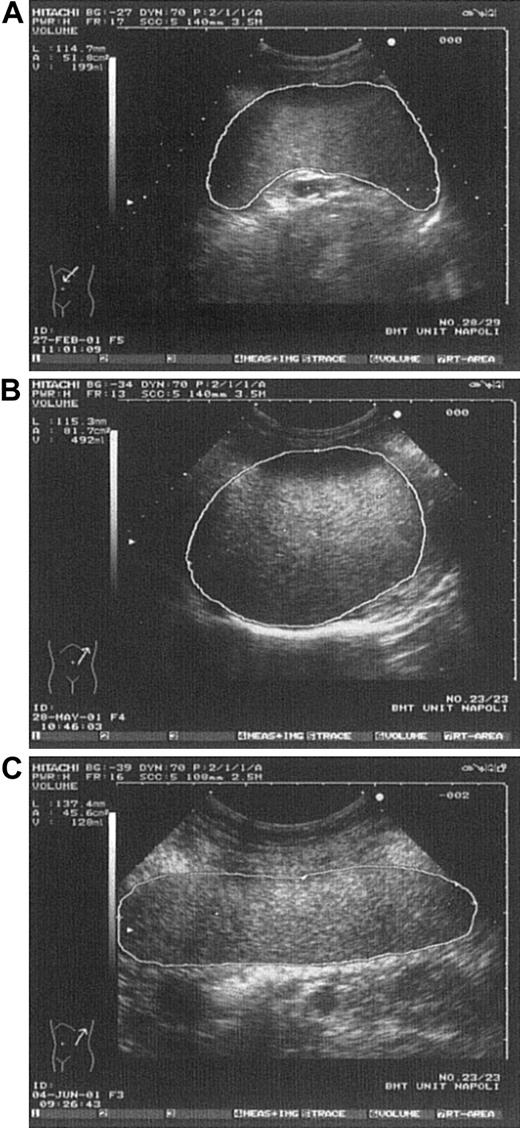

Various spleen shapes detected by US.

(A) Spleen in a control subject having normal longitudinal diameter and volume. (B) Spleen in a thrombocythemic patient having longitudinal diameter like that in Figure 2A but clearly enlarged volume. (C) Spleen in a control subject showing enlarged longitudinal diameter but normal volume (rodlike spleen).